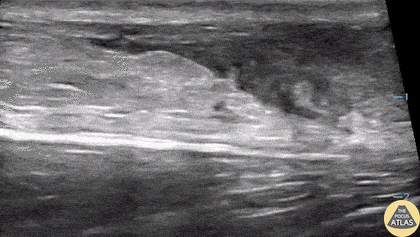

16-year-old male presented with acute onset sharp pain to his LE and inability to bare weight after having landed oddly while playing basketball. POCUS revealed a near-complete disruption of his Achilles Tendon. Paul Khalil, MD. Assistant PEM POCUS director at University of Louisville/Norton Children’s @Khalil3Paul